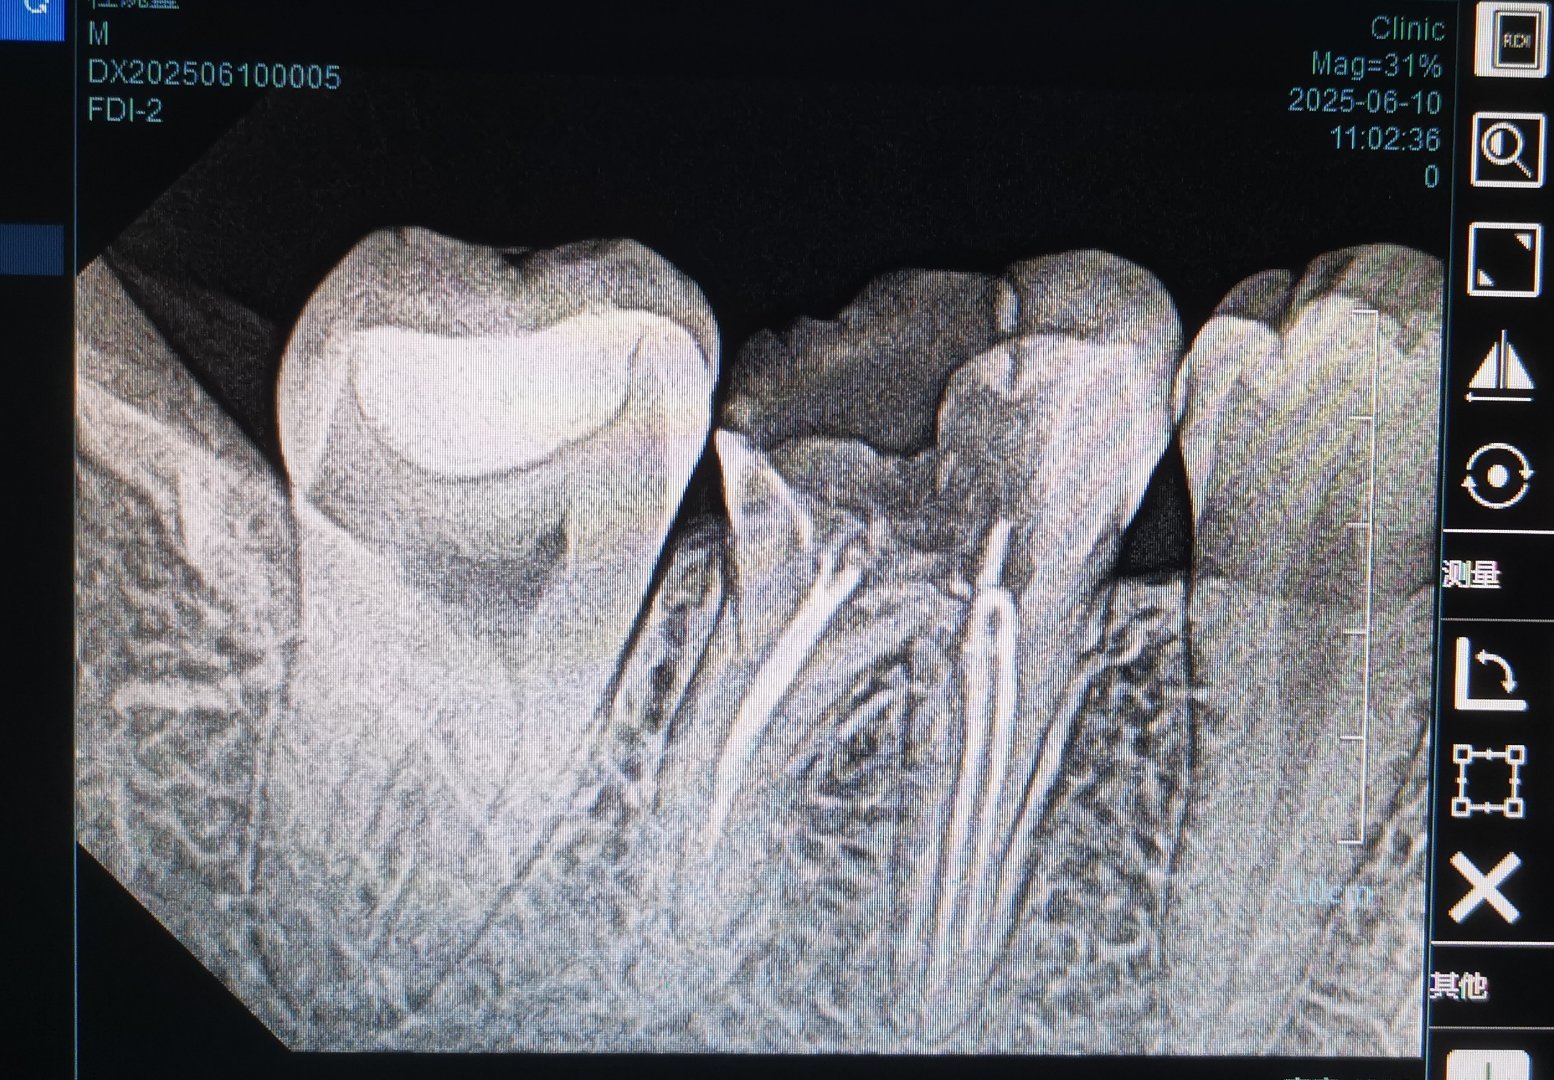

接一例转诊,急性上颌窦炎,发热。 两个月前在一诊所做过根管治疗。我问,当时医生拍

第一眼看过去,你的诊断会是什么?口腔科普